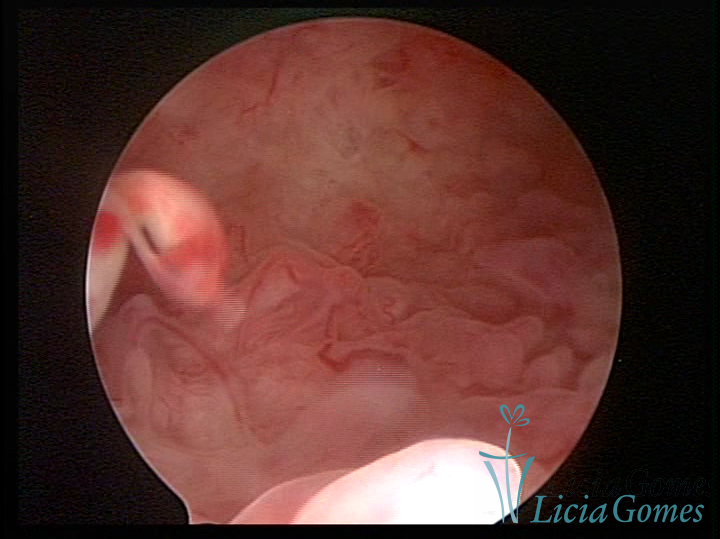

A histeroscopia permite analisar as características da superfície endometrial, não podendo avaliar a profundidade ou o grau de invasão miometrial.

Mas poderá verificar se as lesões são do tipo: focal; regional ou difusa

Este pode apresentar uma gama variável de aspectos macroscópicos, com aspecto pseudopolipoide; lembrando tecido cerebroide ou com reação deciduoide;a vascularização superficial é mais evidente e com vasos em formatos de saca-rolha ou espirais visualizando também a vascularização com atípias, com aumento do calibre dos vasos superficiais, pode ser encontrado também tecido em necrose, poderá haver um pequenos dendritos (papilomatoso).